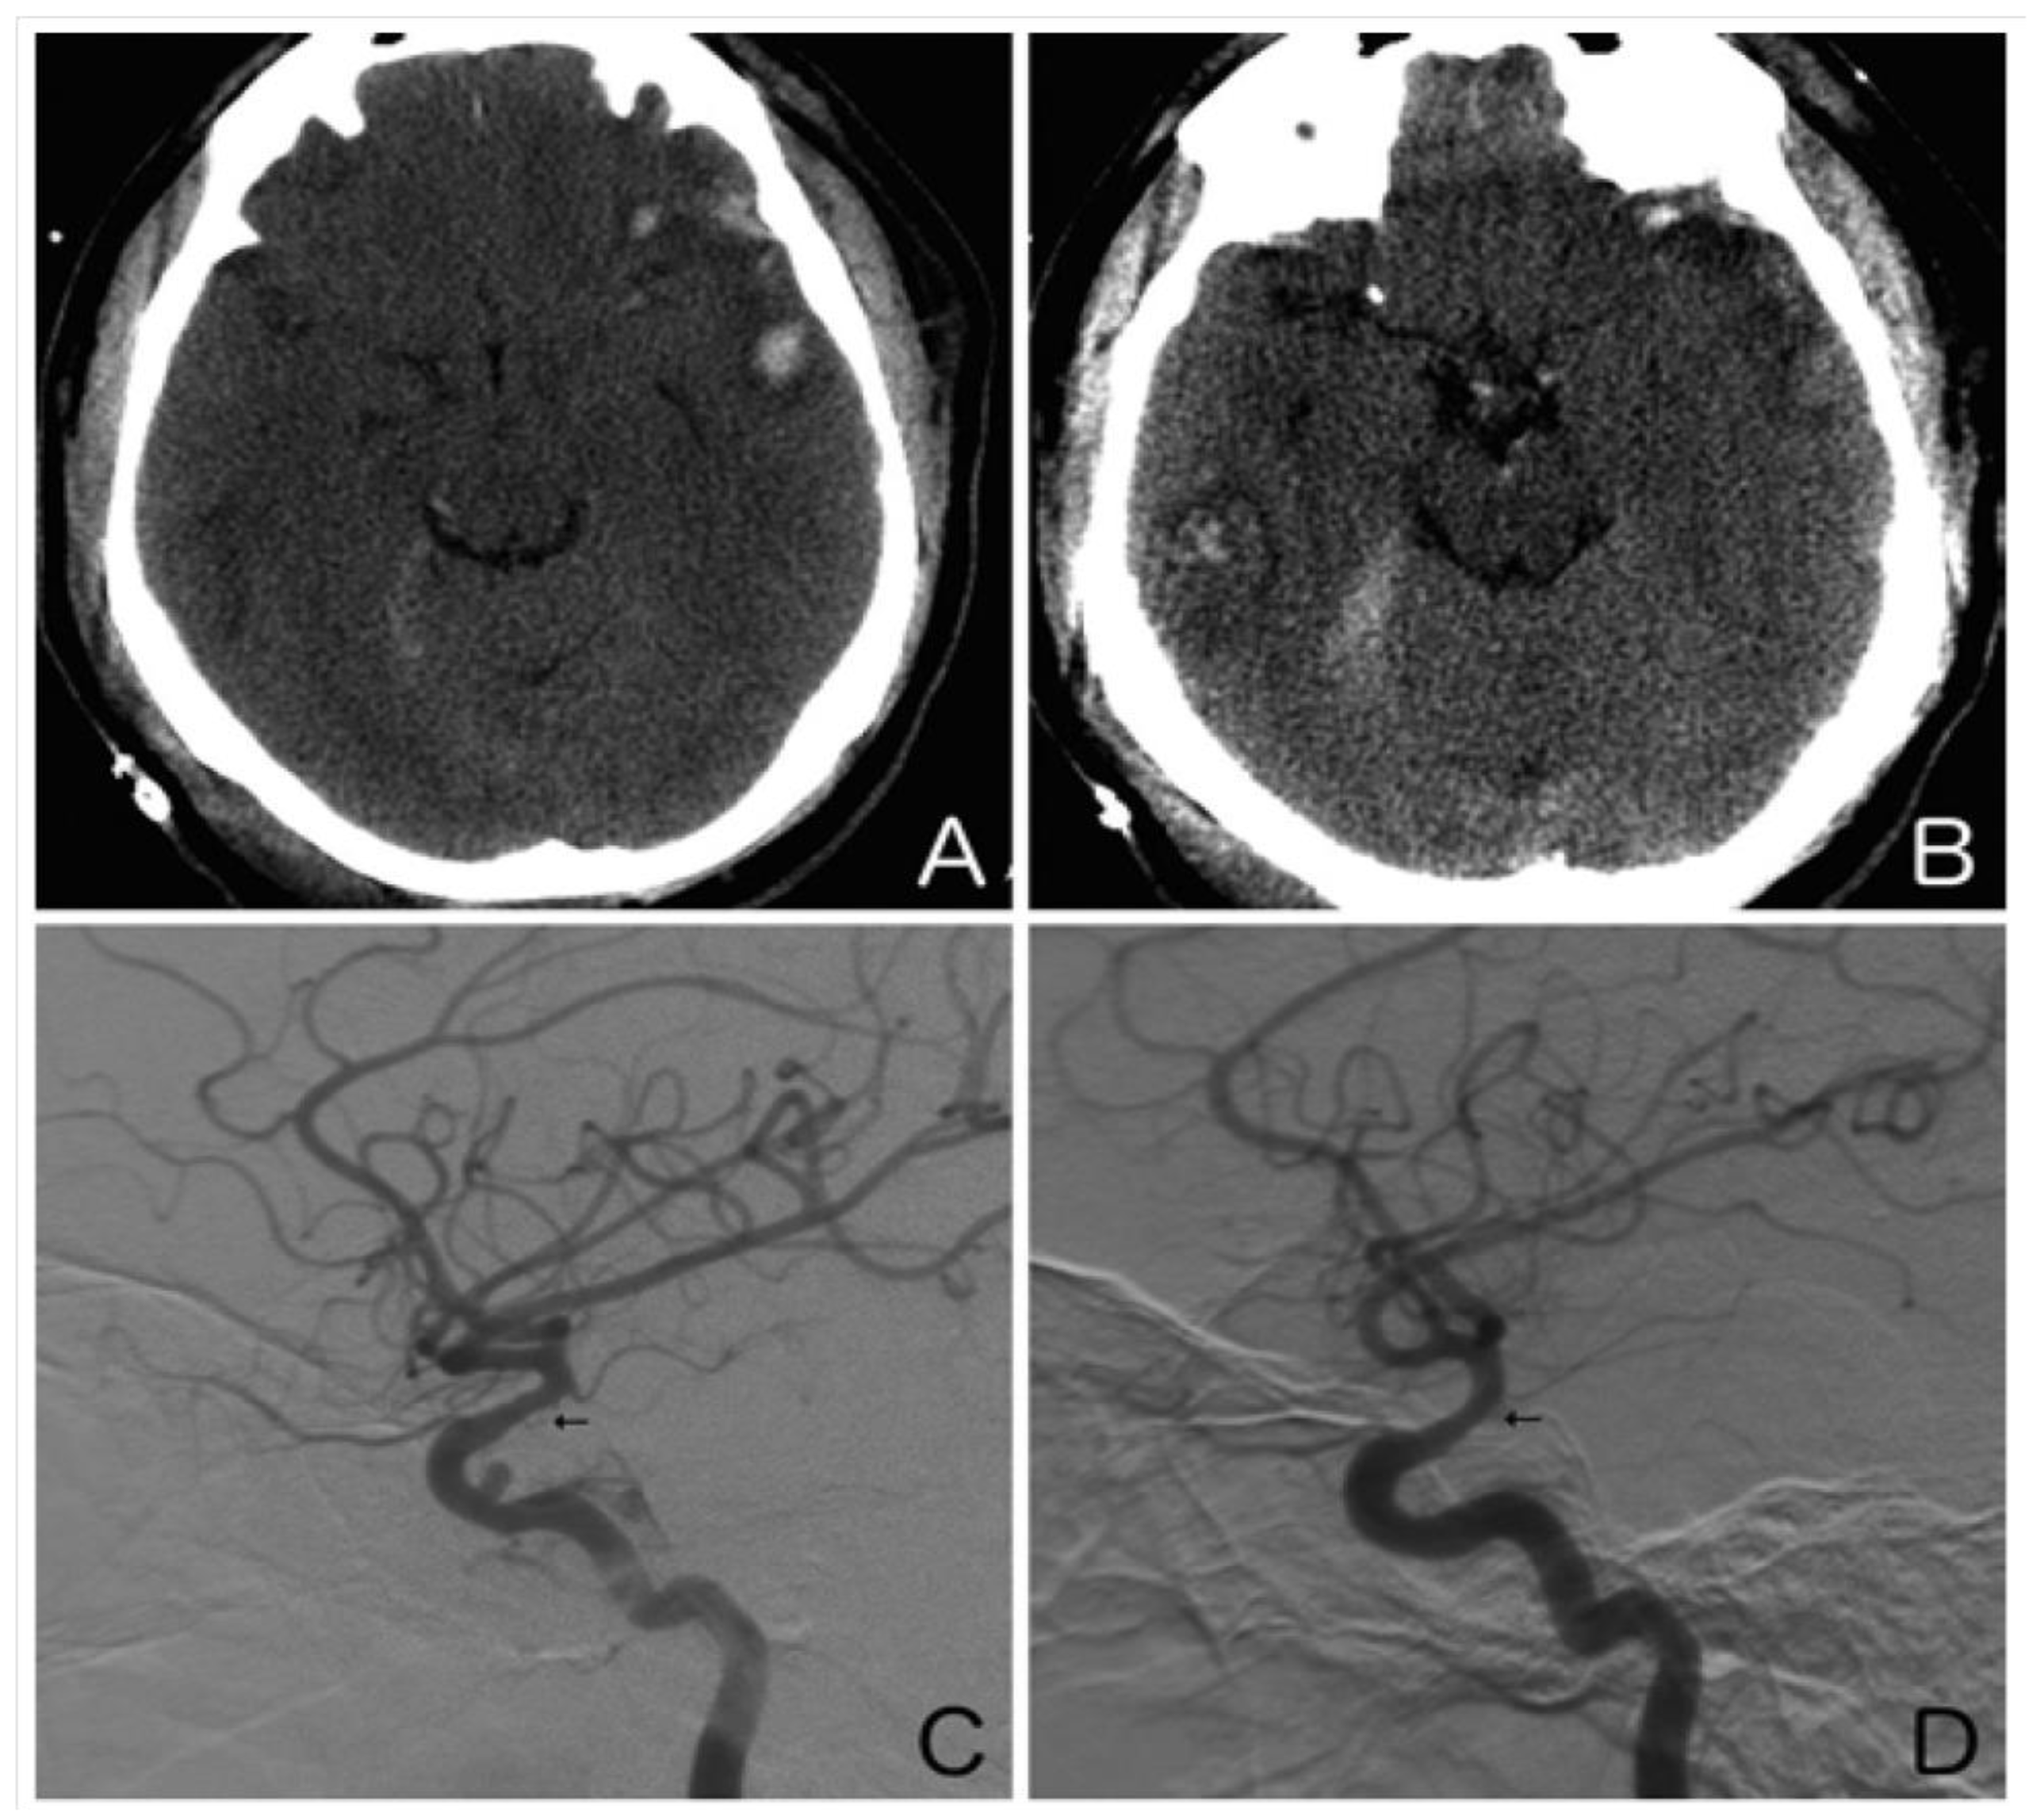

Secondary injury is a cause of substantial morbidity and mortality following traumatic brain injury (TBI), and its impact can be exacerbated by hypotension and hypoxia. Recently, arterial vasospasm has come into focus as a potential contributor to secondary injury via delayed ischemia (Figure 2). Post-traumatic vasospasm (PTV) is hypothesized to result from the release of spasmogenic and neuroinflammatory substances generated by the breakdown of blood products in the subarachnoid space following trauma [42]. In contrast to aneurysmal subarachnoid hemorrhage, surveillance for PTV is not routinely performed, making it difficult to determine its true incidence. As imaging technology has improved, rates of PTV detection in TBI patients have been reported to range from 27% to 63% [43,44]. Diagnosis of PTV is often established using CTA/CT perfusion and DSA. Additionally, by monitoring the mean blood velocity, which acts as a surrogate for cerebral perfusion pressure, transcranial Doppler ultrasonography has been instrumental in guiding the early management of TBI patients [45]. Certain clinical features, such as fever, low Glasgow Coma Scale score, number of cerebral lobes affected by the traumatic injury, high Injury Severity Score, and presence of an associated pseudoaneurysm or hemorrhage, have been shown to correlate with an increased risk of developing PTV [43,46,47,48,49,50].

Illustrative case. A 25-year-old man presented after an assault to the head. An axial non-contrast computed tomography scan of the head showed a left temporal contusion with adjacent subarachnoid hemorrhage (A) and a right temporal contusion and tentorial subdural hematoma (B). Right (C) and left (D) internal carotid artery digital subtraction angiograms (lateral view) obtained on day 10 showed moderate vasospasm of both supraclinoid internal carotid arteries (arrows). Note the traumatic pseudoaneurysm of the cavernous right internal carotid artery.